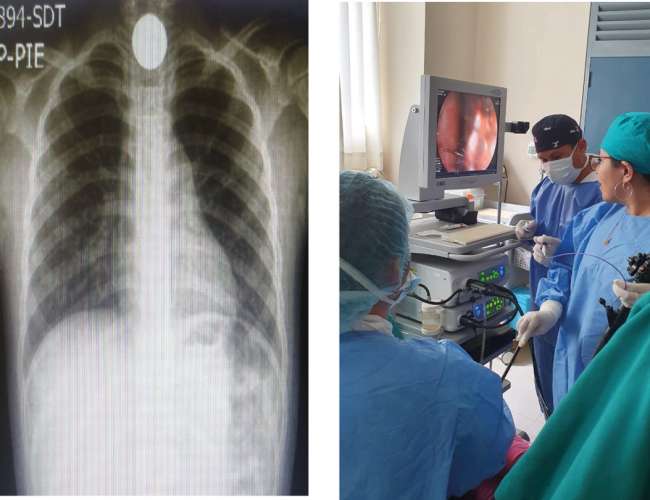

La inocencia de una niña de 6 años de edad y el descuido de personas adultas la llevó a cometer un error que pudo tener un desenlace lamentable, pues la pequeña fémina ingirió tres monedas (de 1.00 Sol 0.20 céntimos, 0.10 céntimos) que obstruyeron su sistema digestivo.

Sin embargo, la rápida intervención de los profesionales de la salud del Hospital Tarapoto, conformado por la Gastroenteróloga, Karol Valdivia López, el Médico anestesiólogo Jorge Ríos Barrera, Licenciados en enfermería y técnicos en enfermería, ayudados por equipos modernos (Fujinon 4450/ endoscopio EG 530WR) y pinza en diente de ratón, pudieron realizar con éxito el procedimiento: endoscopia alta con extracción de cuerpo extraño y así establecer la salud de la infante.

Tras la intervención que duró aproximadamente 30 minutos, la paciente pasó a observación para luego recibir el alta médica respectiva y seguir su proceso de recuperación en la calidez de su hogar.